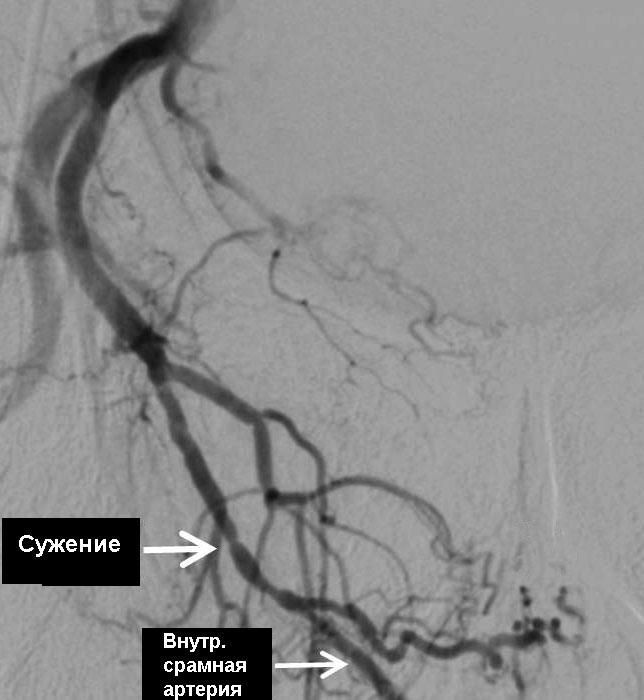

В 80% случаев причина носит СОСУДИСТЫЙ характер. Как было объяснено выше, в случае нарушения притока крови к половому члену, НАСТУПАЕТ ЭРЕКТИЛЬНАЯ ДИСФУНКЦИЯ. Основной причиной снижения притока крови служит сужение просвета приводящих артерии в результате атеросклеротического процесса в стенке артерии.

Если причиной эректильной дисфункции является недостаточный приток крови по артериям в половой член, то диагноз ставиться на основании специального исследования этих артерии – АНГИОГРАФИИ. В случае наличия сужений или закупорок в приводящих артериях, они четко видны на ангиограммах.

Мы исходим из фундаментального правила – устранить причину, а не лечить косвенным путем, как, например, действуют общеизвестные лекарства Виагра или Сиалис. В нашей клинике мы предлагаем современную и высококвалифицированную диагностику сосудистой системы таза и гениталий и, в случае наличия показаний (сужения или закупорки артерии), мы устраняем эту причину с помощью малоинвазивного (без хирургической операции) лечения – расширения суженных артерии и их внутрипросветного протезирования.

Как делается ангиопластика и протезирование артерии? . . .

После прокола артерии на бедре, в просвет сосуда вводится специальный зонд катетер, который подводится прицельно к артериям, кровоснабжающим половой член. После диагностики артерии и обнаружения сужения, в зону поражения артерии подводится миниатюрный баллонный катетер и сужение устраняется после раздувания баллончика. После сдувания и удаления баллона, на месте расширенного участка артерии ставится специальный каркас, который закрепляет результат и удерживает просвет артерии в раскрытом состоянии, нормализуя таким образом кровоток через расширенный и протезированный участок артерии. Указанная операция делается без общего наркоза и разрезов, только под местной анестезией с помощью маленького прокола (2-3мм) в бедренной артерии. В результате такого неинвазивного вмешательства нормализуется кровоток и, соответственно, нивелируется сосудистая причина эректильной дисфункции.